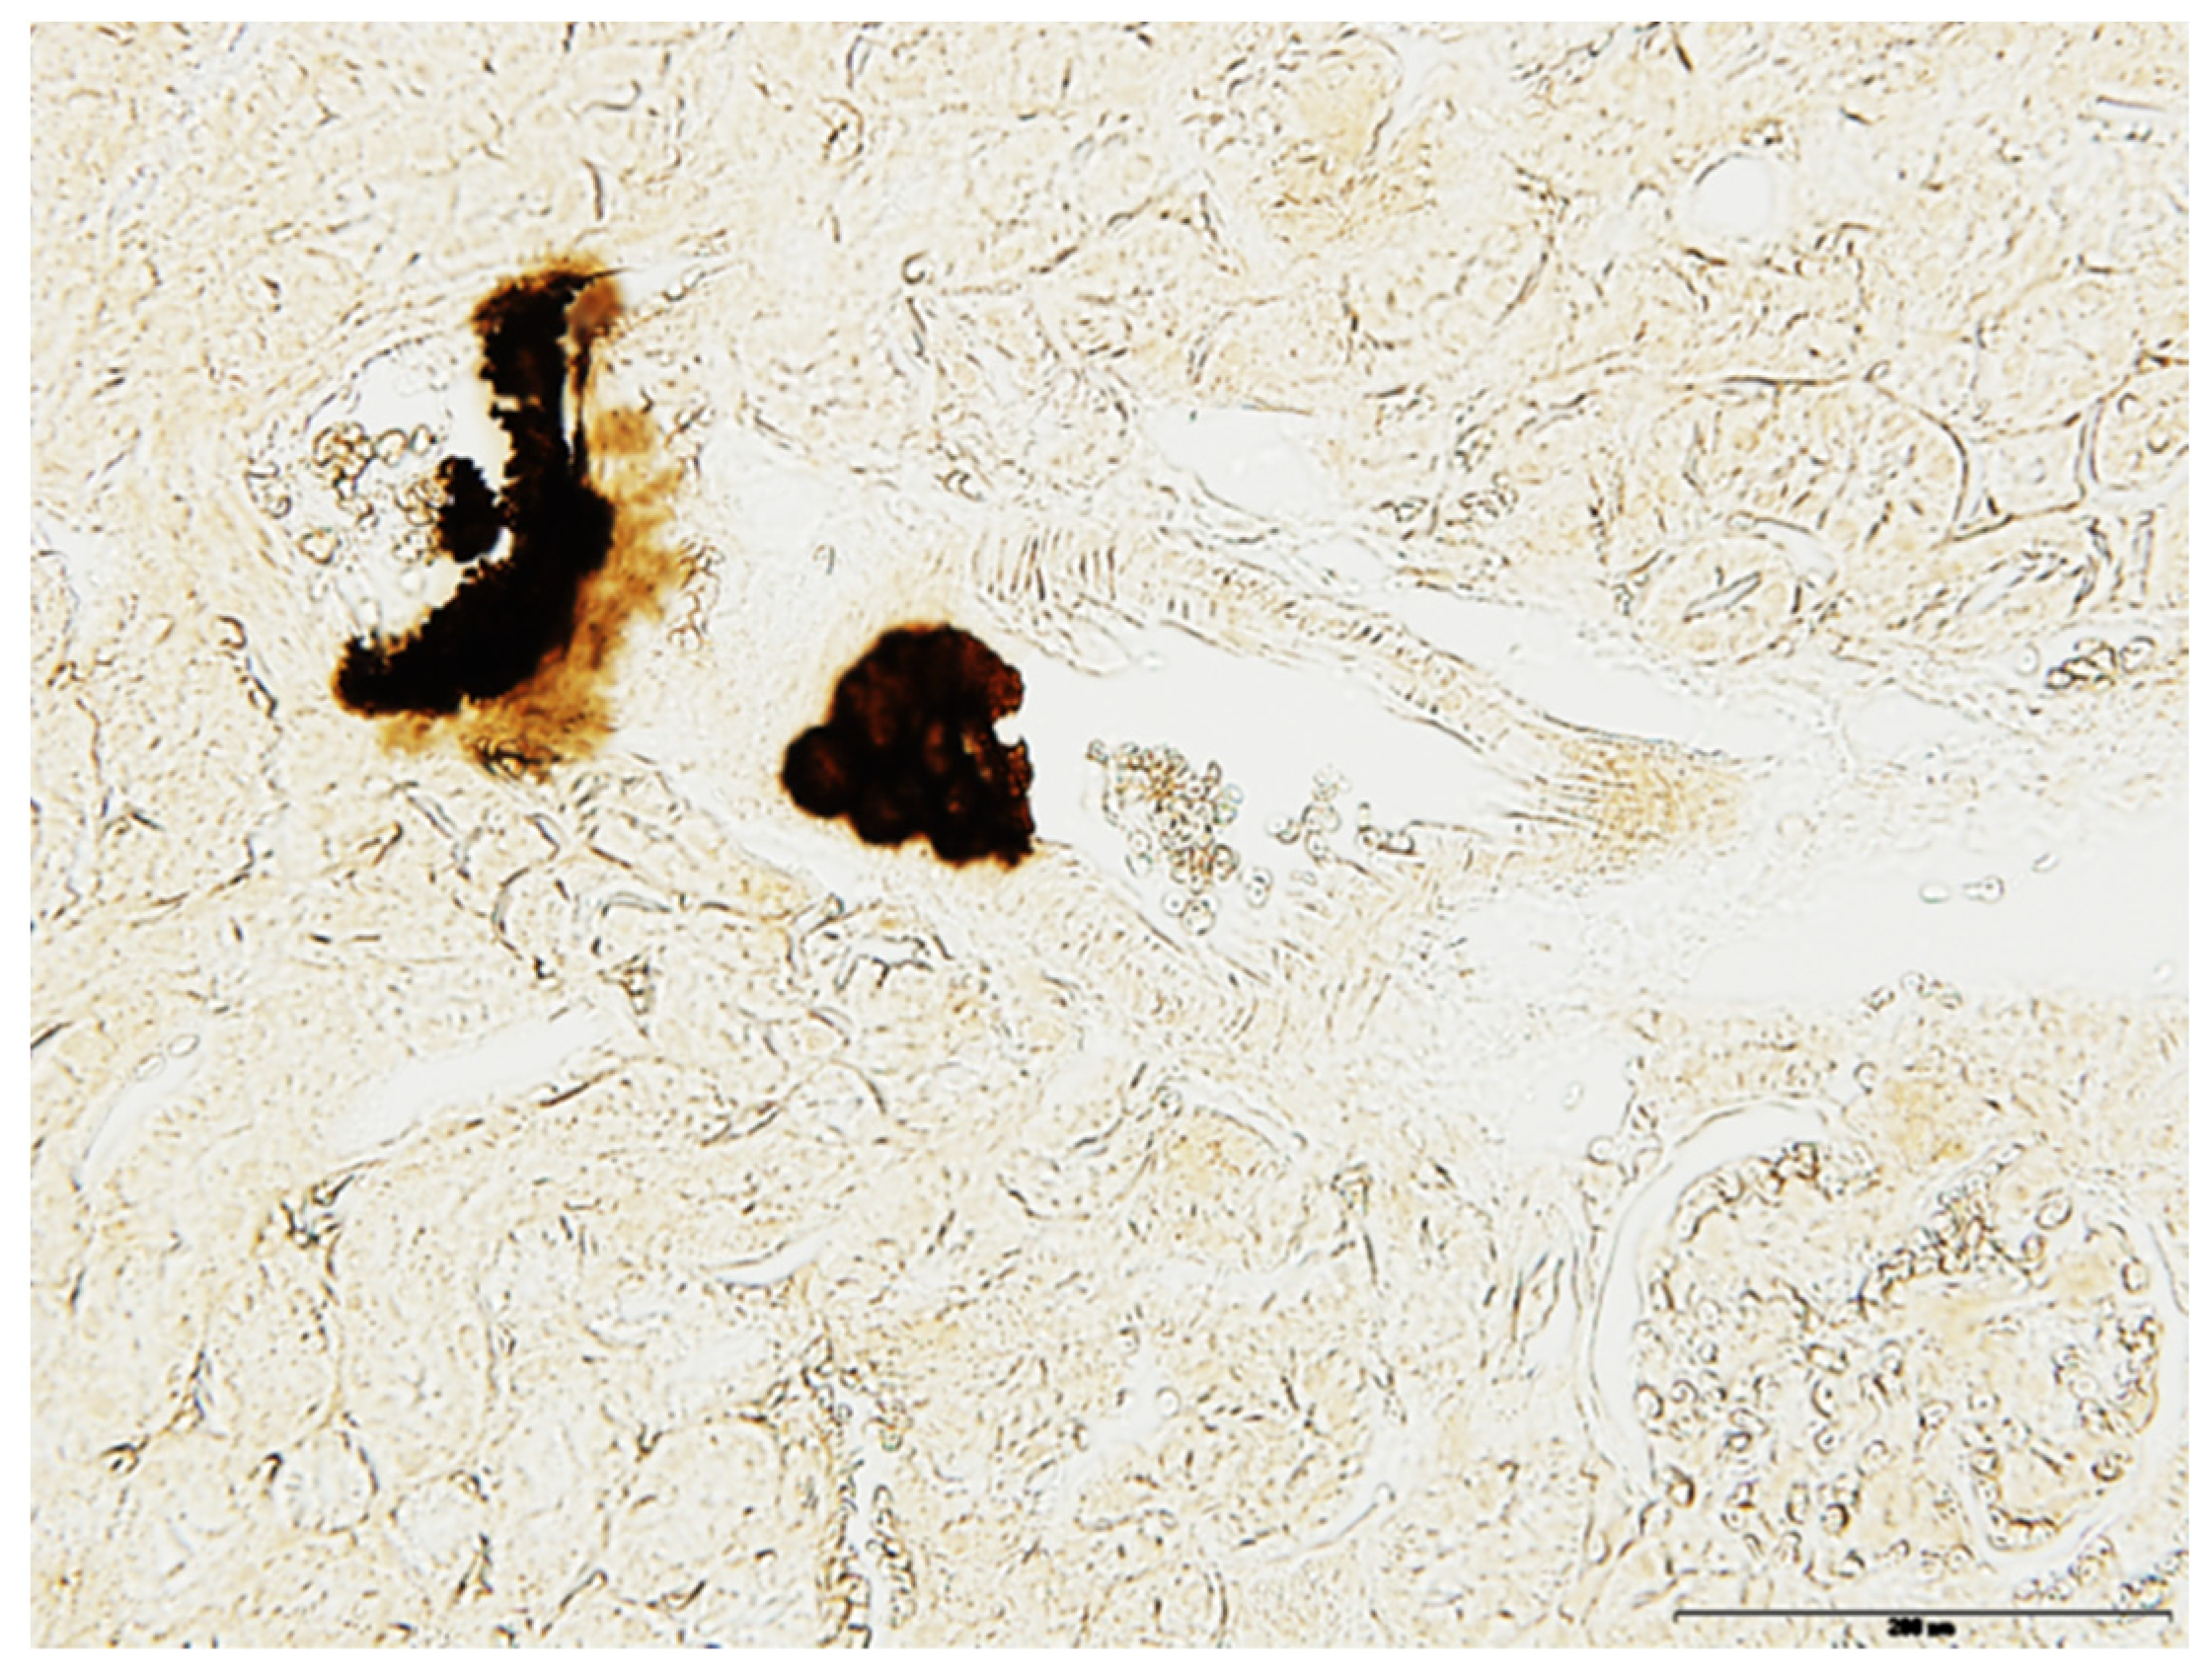

- Histopathological analyses and Yasue staining evidenced that calcifications were initiated in the close vicinity of elastic fibers in the aortic media, as observed in PXE patients, and were not atherosclerotic lesions (Figure 2). To go further in the characterization of the crystalline phases, we gathered observations through scanning electron microscopy coupled with energy-dispersive X-ray spectroscopy (SEM-EDS), evidencing that deposits on elastic fibers contained high amounts of calcium and phosphate (Figure 2). OPTIR experiments using the mIRage experimental setup identified that incipient calcifications were made of carbonated apatite (Figure 2). The analysis of the spectra revealed some features specific to the presence of different absorption bands of biological apatite which has the general chemical formula Ca10−x□x(PO4) 6−x(CO3)x(OH)2−x□x with 0 < x < 2), including the ν3 P-O stretching vibration mode measured at 1035–1045 cm−1 (Figure 2). Carbonate ions were detected together with apatite by their ν3 C-O stretching vibration mode around 1420 cm−1.

- Histological examination and Yasue staining of kidneys revealed that cortical calcifications were actually arterial calcifications (Figure 4). The use of µFTIR techniques also evidenced that these calcifications were made of carbonated apatite, with typical absorption bands.